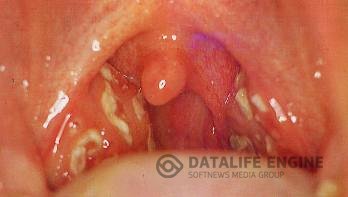

Ангина - лечение народными средствами

Ангина общее острое инфекционное заболевание, при котором воспалительные явления выражены главным образом в лимфоидной ткани глотки. Ангина — одно из самых распространенных заболеваний верхних дыхательных путей. По частоте она занимает второе место после гриппа и острого катара верхних дыхательных путей. Болеют ангиной преимущественно дети дошкольного и школьного возраста, а также взрослые до 35—40 лет. У людей старческого возраста ангина наблюдается редко.

Различают следующие основные виды ангин: катаральная, фолликулярная, лакунарная, флегмонозная. Нельзя думать, что ангина — одно из самых легких заболеваний. Часто она дает осложнения в виде ревматизма, нефрита, может перейти в острый бронхит и воспаление легких. Основными признаками заболевания являются боль и першение в горле, высокая температура, общее плохое самочувствие.